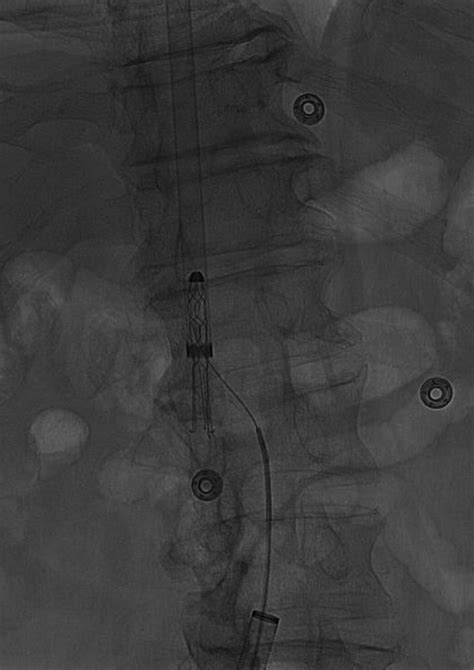

At its core, the IVC Greenfield Filter is a cone-shaped, metallic device inserted into the inferior vena cava, typically via the jugular or femoral vein. It is engineered to trap emboli—or blood clots—before they can enter the heart and subsequently the lungs, where they would cause a pulmonary embolism (PE). Unlike many other filters, the Greenfield design is renowned for its ability to maintain high flow rates while effectively catching clots, a feature that significantly reduces the risk of the filter itself causing a blockage.

• Conical shape: This geometry allows the filter to catch clots without completely occluding blood flow.

• Leg anchors: These secure the filter to the vein wall, preventing migration.

• Material composition: Initially stainless steel, modern iterations often use titanium or other biocompatible alloys to improve compatibility and visibility under medical imaging.

Techniques for placing and retrieving these devices have evolved significantly. With the use of ultrasound and fluoroscopic guidance, interventionalists can place the IVC Greenfield Filter with extreme precision through minimally invasive entry points. This has dramatically shortened recovery times and reduced the physical trauma associated with vascular procedures. Modern practice focuses heavily on the "retrieval phase," ensuring that patients are scheduled for follow-up appointments to discuss the removal of the device the moment their clinical condition allows.